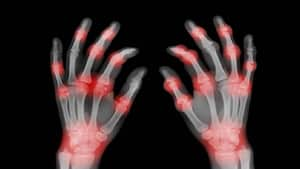

La osteoartritis o artrosis es un tipo de artritis que solo afecta las articulaciones, usualmente en las manos, las rodillas, las caderas, el cuello y la parte inferior de la espalda, de acuerdo con Medline Plus, la Biblioteca Nacional de Medicina de Estados Unidos.

“En una articulación sana, los extremos de los huesos están cubiertos con un tejido suave y resbaloso llamado cartílago. El cartílago protege los huesos y les ayuda a deslizarse fácilmente cuando mueve la articulación. Con la osteoartritis, el cartílago se rompe y se vuelve áspero. En ocasiones, todo el cartílago se desgasta y los huesos se frotan entre sí, y pueden crecer protuberancias de hueso adicional en el área de la articulación llamadas espolones óseos”, explica la Biblioteca.